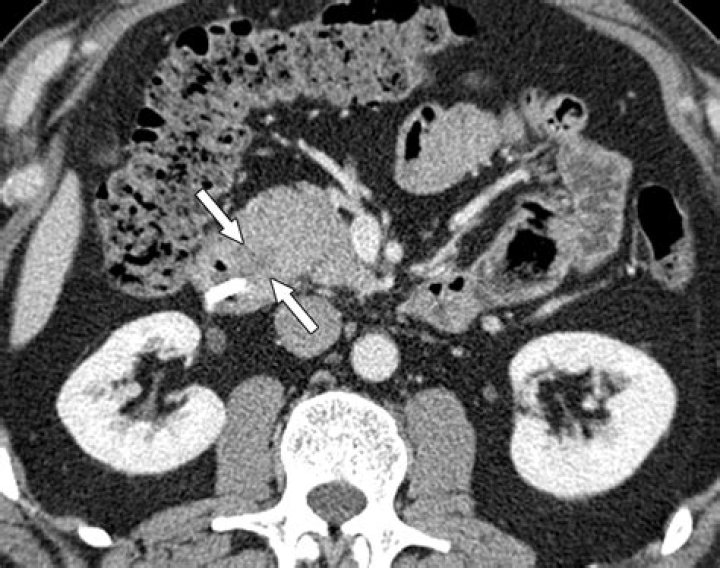

Does CT scan show autoimmune pancreatitis?

A relatively specific main pancreatic duct change of AIP is multifocal narrowing, and this may be depicted on CT or MRCP (1, 19).